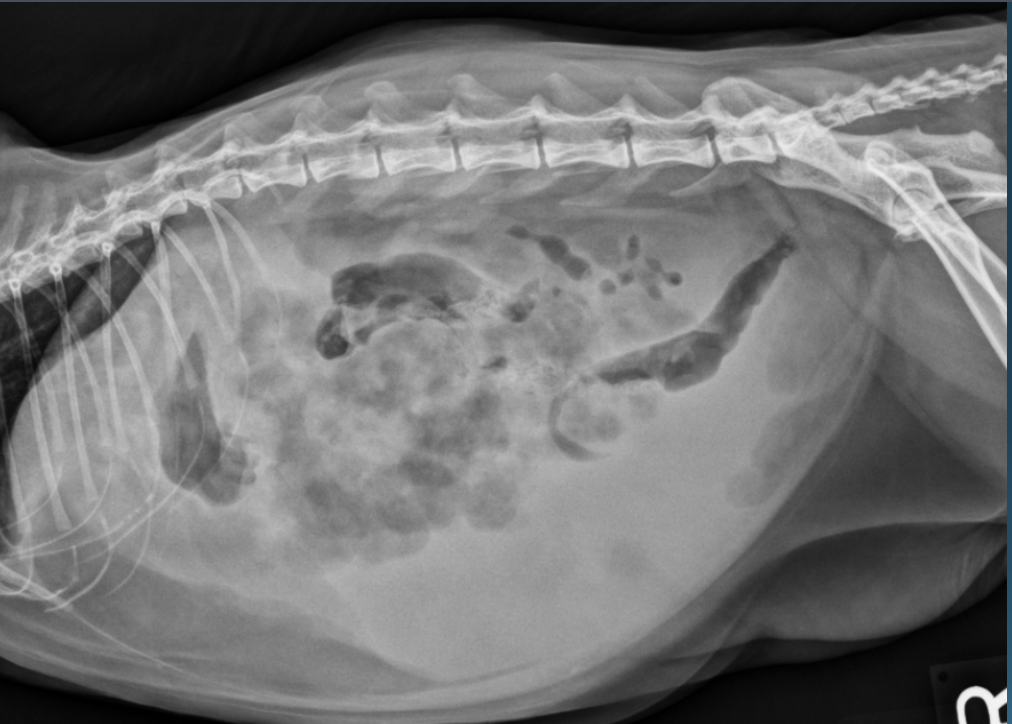

What is shown in these images?

peritonitis

26